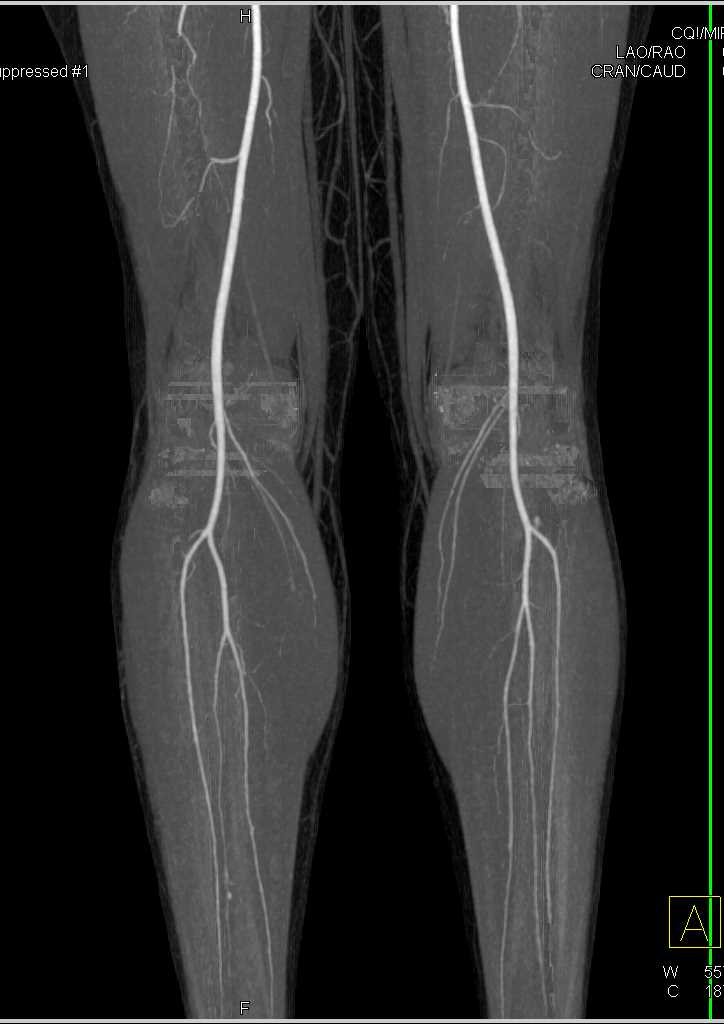

Carcinoid in the Root of the Mesentery Encases the SMA